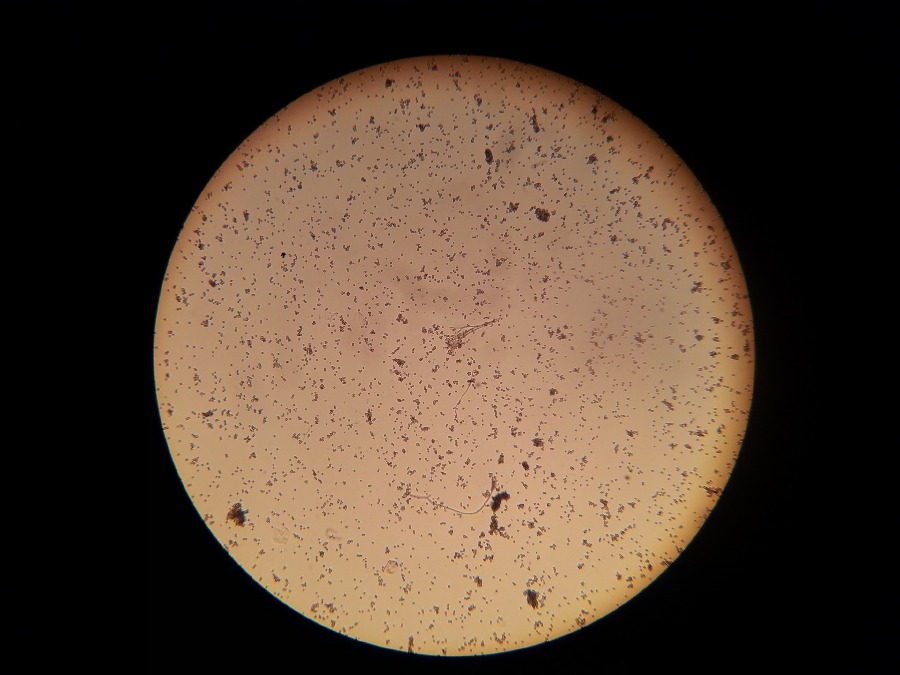

La listeria è un batterio che di solito causa una malattia lieve, ma può essere pericoloso per le donne in gravidanza o le persone con un sistema immunitario debole. Inizia con sintomi simil-influenzali tra cui brividi, febbre e dolori muscolari. Possono essere necessarie fino a sei settimane dopo aver consumato cibi contaminati, perché si verifichino i sintomi.